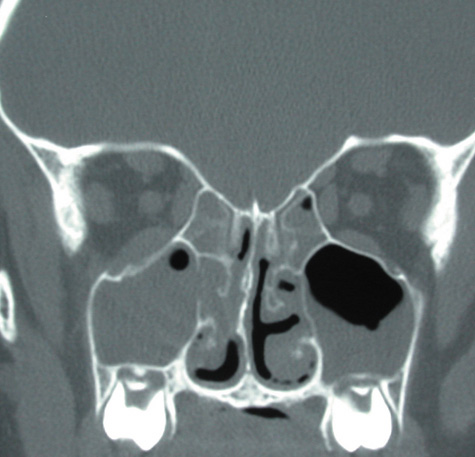

Routine skull films and polytomography have been supplanted by CT in the evaluation of patients with orbital cellulitis.57 CT allows the clinician to differentiate a preseptal cellulitis from an orbital cellulitis.58 If orbital cellulitis has resulted from adjacent intercurrent sinus infection, the diagnosis can be made and the extent of the sinus disease estimated. Sinuses may show changes of osteomyelitis with blurring of the osseous margins of the sinuses, air–fluid levels, or inflammatory tissue within the normally aerated sinus.59 Central nervous system complications can be assessed by neuroimaging, and progression of disease can also be monitored.58

CT should be performed using thin-section (2–4 mm) high-resolution scanning with multiple views of both bone and soft tissue detail.53 Axial and coronal views should be obtained; in one-third of patients with subperiosteal abscesses, the abscess was seen in the coronal sections only.18 Helical CT is a fairly new technology that allows increased resolution with decreased imaging time.60 This type of scan may be especially beneficial in children because of the ability to obtain good imaging with a shorter imaging time.60 elica He HhIntravenous contrast material is not advocated at all centers because there is intrinsically high contrast between infectious changes and orbital fat. However, some authors believe that it is essential to the diagnosis, and it thus remains the preference of the individual clinician, as well as the neuroradiologist.22,59,62

With preseptal inflammation, CT demonstrates soft tissue swelling of the eyelids and tissue adjacent to the orbital septum (Fig. 15). The orbit is not involved, and usually the sinuses do not show evidence of inflammation. The distinction between inflammatory preseptal cellulitis and edema cannot be made.63

Fig. 15. Computed tomography showing preseptal cellulitis of left eye. Note that all swelling is anterior to the orbital septum.

An extraconal or intraconal mass may be present in orbital cellulitis. Proptosis also may be visible. In particular, with intraconal involvement, proptosis is seen with obliteration of the normal soft tissue shadows. “Patchy enhancement” of the intraconal fat in orbital cellulitis has been described.59 The rectus muscles, particularly the medial rectus, and the optic nerve may be thickened.58

CT is particularly useful for imaging orbital and subperiosteal abscesses. Because the periorbit is not adherent to the orbital walls except at the suture lines, an abscess lifts the periorbit, creating a convexity in the orbital periosteum (Fig. 16). Usually subperiosteal abscess formation occurs adjacent to the involved sinus,25,64 but occasionally it occurs at a remote location such as the superolateral orbit.65 Gas may be found within a subperiosteal abscess or within the orbit, arising either from gas-forming bacilli or free communication with sinus air or from prior trauma (Fig. 17). 57,66 CT cannot accurately predict whether a subperiosteal mass represents exudate, inflammatory transudate, or hematoma.67,68

Fig. 16. Computed tomography showing subperiosteal abscess formation. Note elevation of orbital periosteum and convexity as pus elevates periorbit from the medial orbital wall.